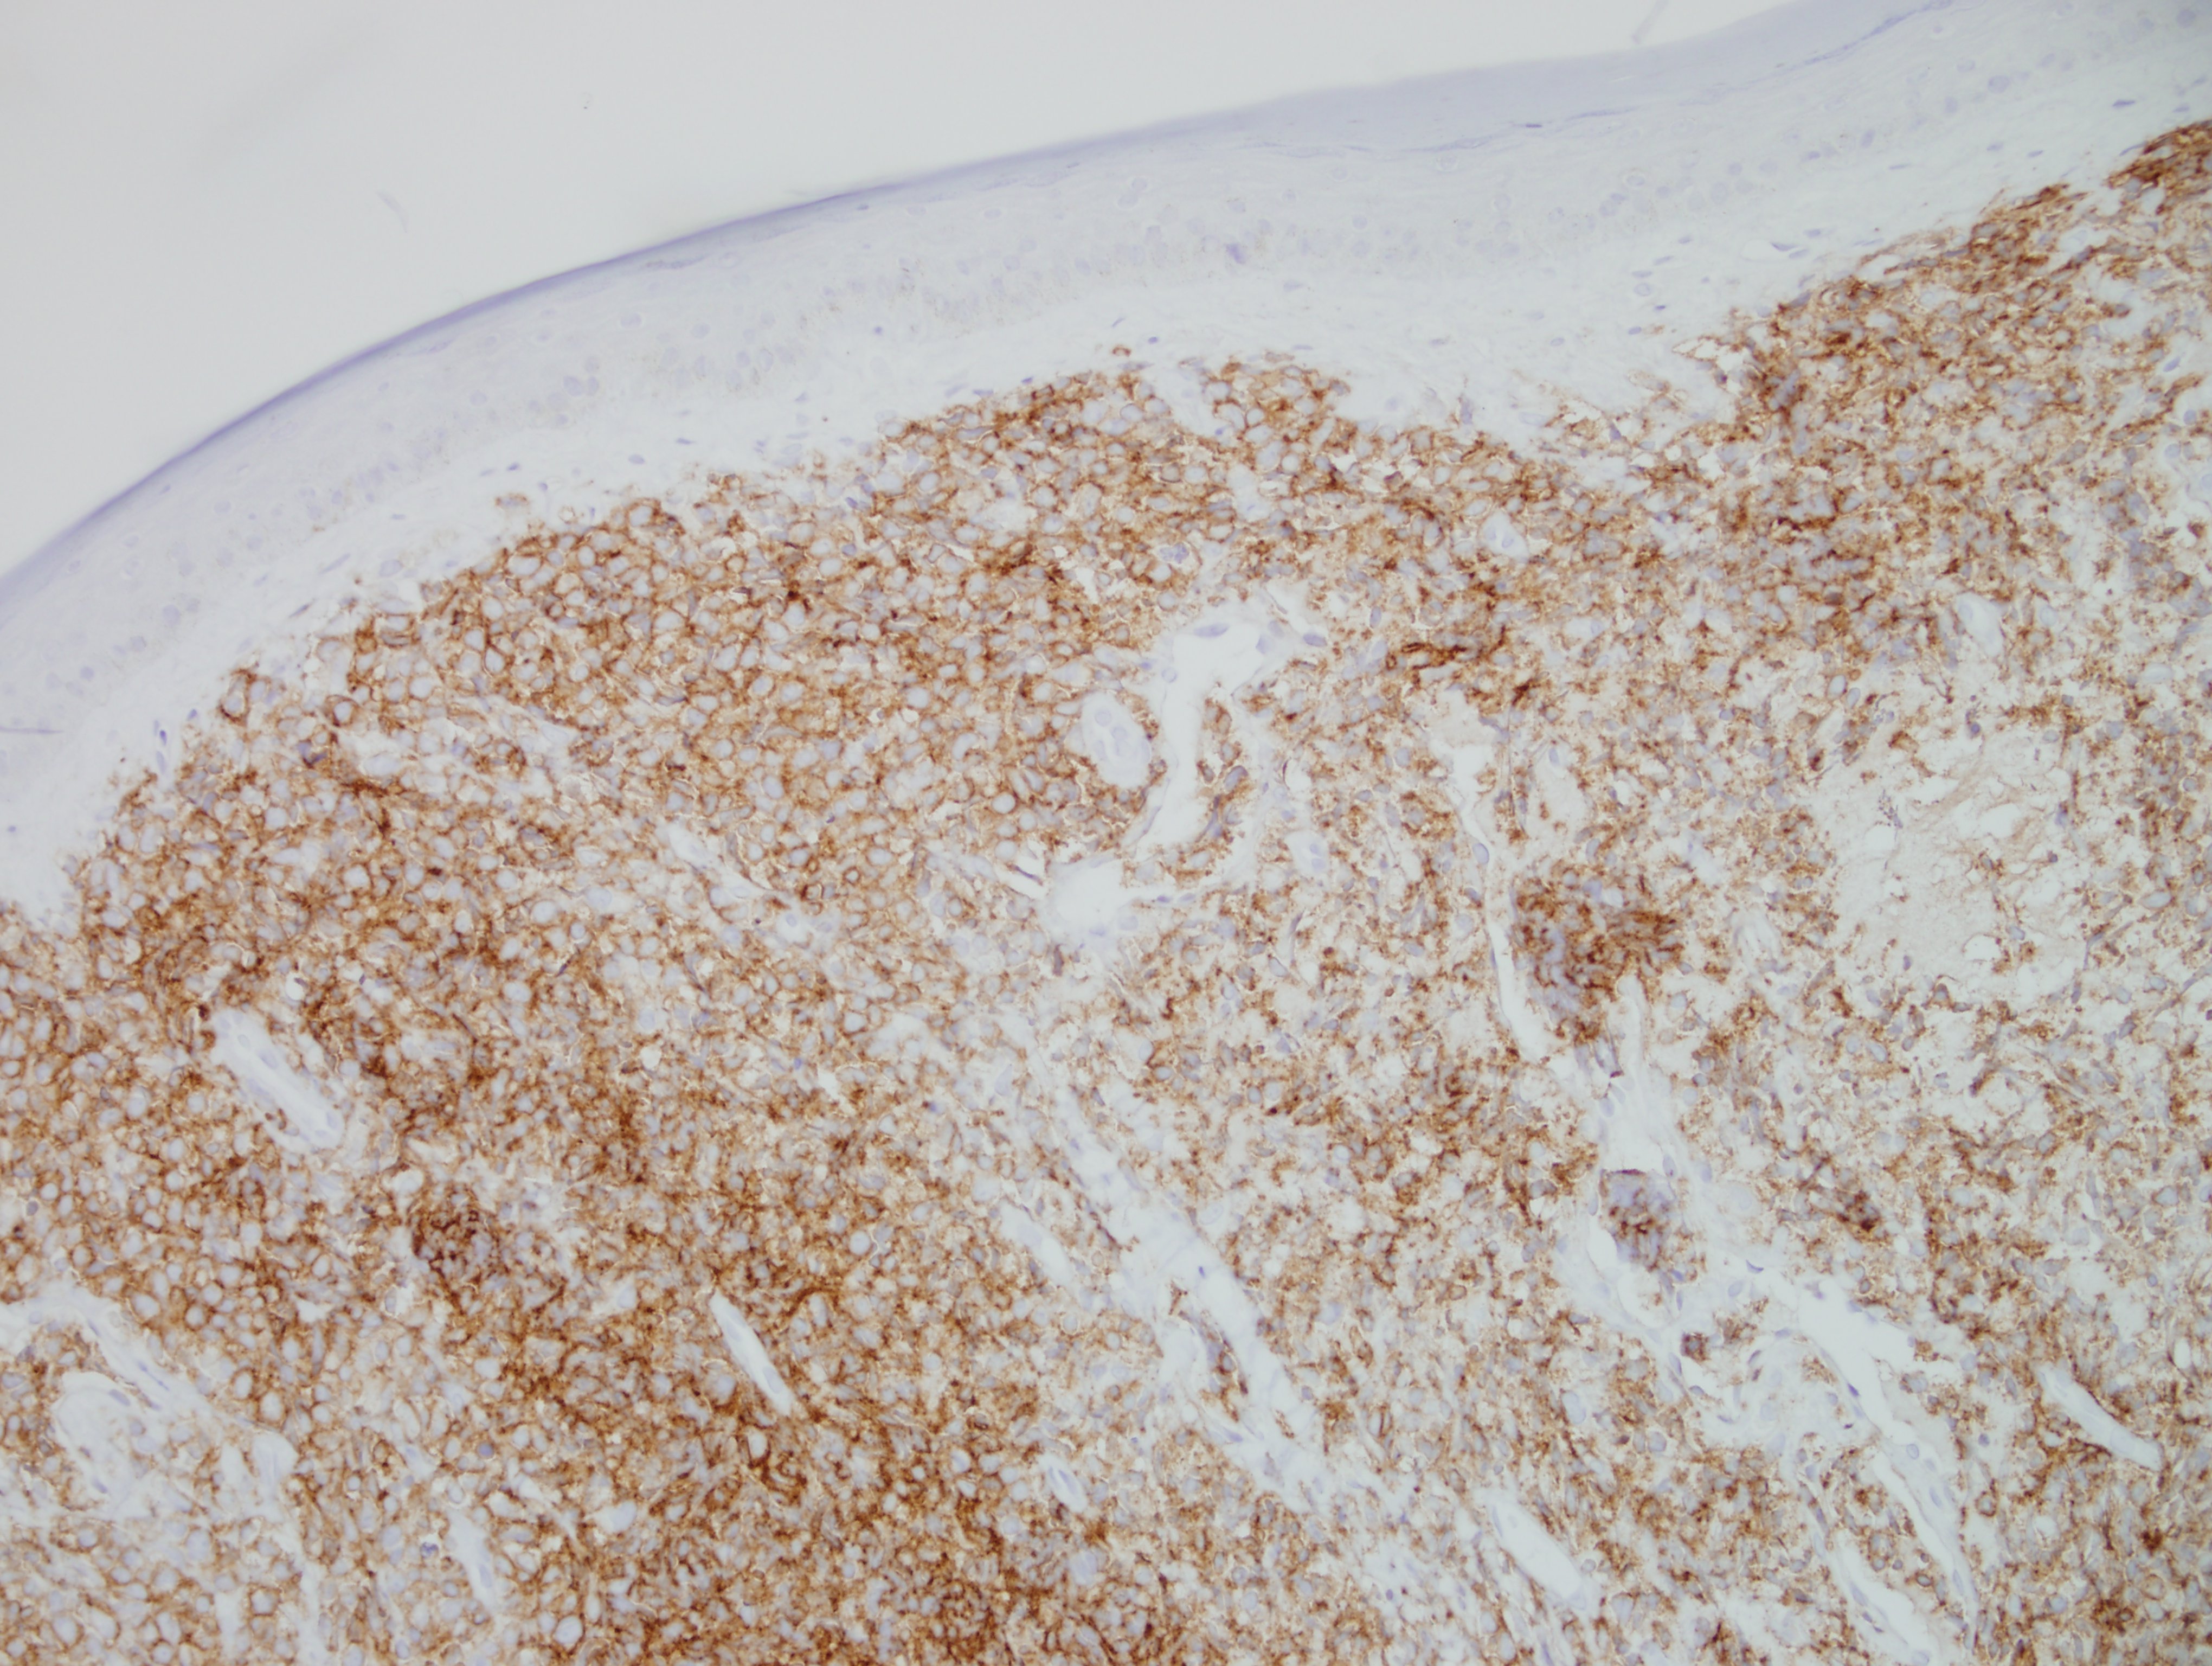

Morphologically, BPDCN is characterized by a diffuse infiltrate of blastoid, monomorphic and medium-sized cells with scant cytoplasm, irregular nuclei, fine chromatin, and nucleoli. Mitoses are typically present and necrosis is usually absent. With cutaneous manifestations, epidermotropism is not observed. Tumor cells typically express CD4, CD7+/-, CD56, CD123, CD303, TCL1, and CD43. Very rarely, CD56 can be negative. CD33, CD79a, BCL2, and BCL6 can also be expressed. T-cell and B-cell receptor genes are usually germline. Several recurrent chromosomal abnormalities have been noted, such as 5q21/5q34, 12p13, and 13q13-21.